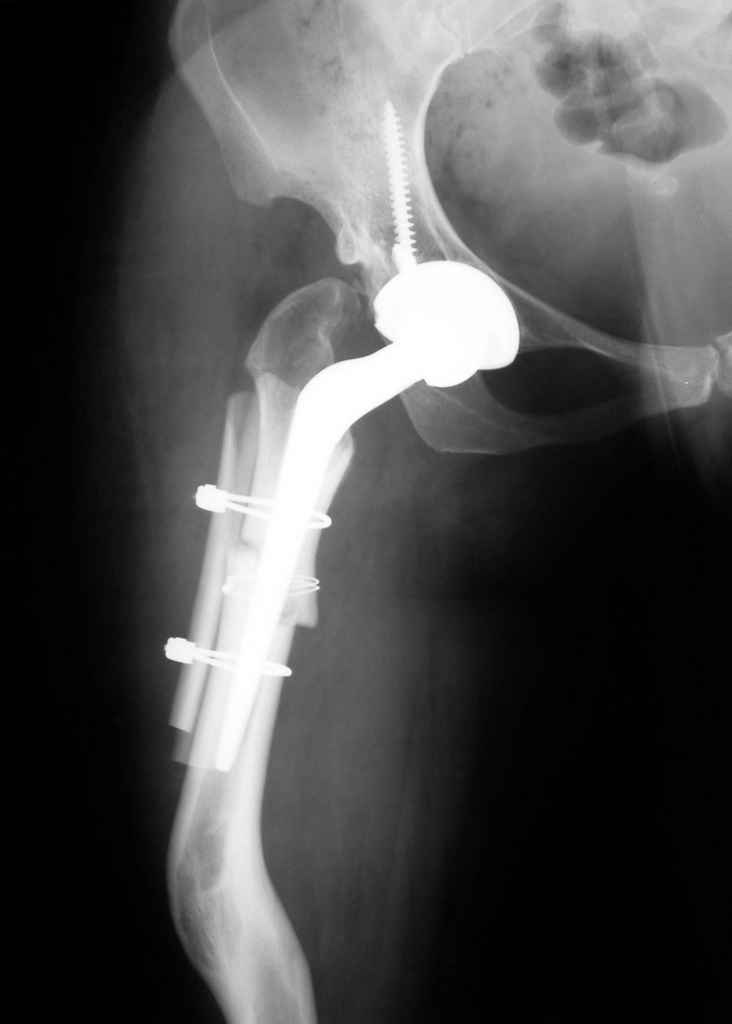

Поднят очень интересный вопрос об эффективности создания опорного бедра по Илизарову у молодых пациентов (ок). Наверное мне не повезло и я не

видел положительных результатов после этих операций, а вот проблемных больных приходится видеть достаточно часто. Причем сроки их обращения

после остеотомии короткие - 3-5 лет, а выполнение эндопротезирования после остеотомии на двух уровнях с многоплоскостной деформацией является

серьезным испытанием и для пациента и для хирурга. Я тоже не сторонник эндопротезирования в молодом возрасте, но уж после неудачных остеотомий

остеотомии. Я представил Р-граммы больных с неудачными р-ми после остеотомий.

Эндопротезирование у них было на порядок сложнее в отличие от артропластики без проведения остеотомии.